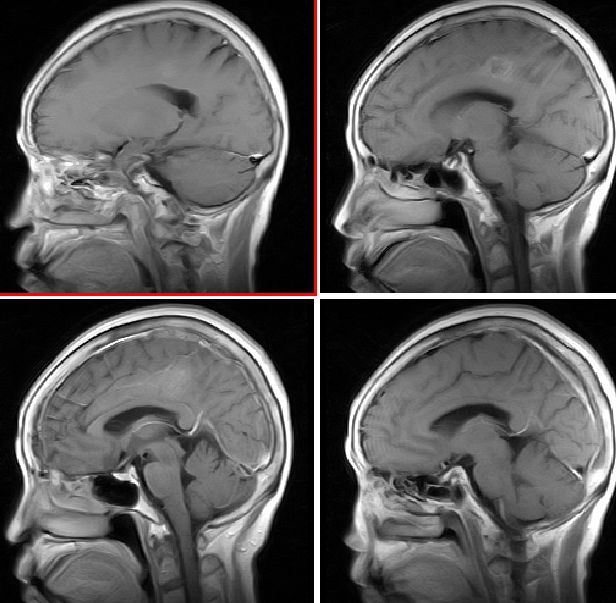

mri增强

mr表现:中央旁小叶区病灶号不均匀性稍长t1、长t2信号,病灶周边见稍短t1信号环。右侧脑室体旁见点片状等t1、稍长t2信号影。flai序列各病灶均呈高信号。增强后右侧中央旁小叶区病灶呈不均匀性强化。